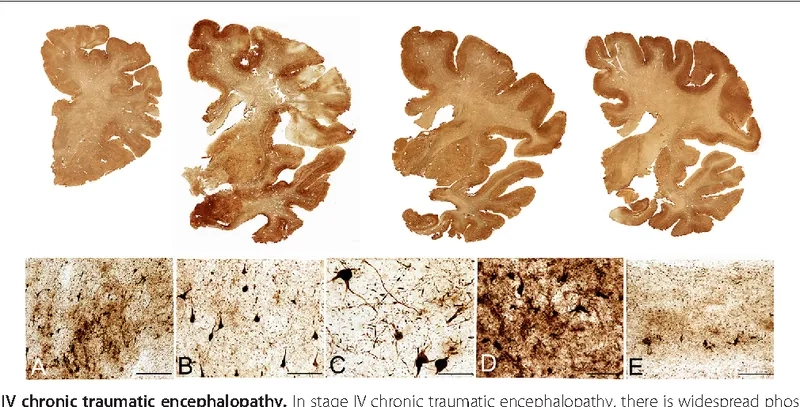

- The accumulation of an abnormal protein called tau forms clumps that slowly spread throughout the brain, killing brain cells and leading to progressive decline.

- As the disease progresses, cognitive impairment becomes more pronounced, with individuals experiencing significant memory loss, confusion, and impaired judgment, which can resemble Alzheimer's disease.

- In later stages, motor symptoms may develop, including tremors, slowed movement (parkinsonism), and difficulty with speech and swallowing, reflecting widespread brain damage.

Visualizing concepts related to CTE